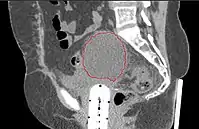

- Seen postoperatively in up to 30% of GYN surgeries with pelvic/para-aortic LND

- Believed to arise from surgical transsection or inadequate ligation of draining lymphatics

- Lymphatic fluid may accumulate in various pelvic and retroperitoneal compartments

- Small lymphoceles typically resorb spontaneously

- Large lymphoceles may cause compression symptoms, and may result in abdominal distention, abdominal and pelvic pain, hydronephrosis, bladder dysfunction, constipation, tenesmus, edema of the ipsilateral leg and of the genitalia, and thromboembolism of iliac vessels

- Infection may cause fever, chills, and sepsis

- Symptomatic lymphoceles are typically managed initially with percutaneous CT-guided drainage, surgical therapy may be required

- Postoperative Lymphocele